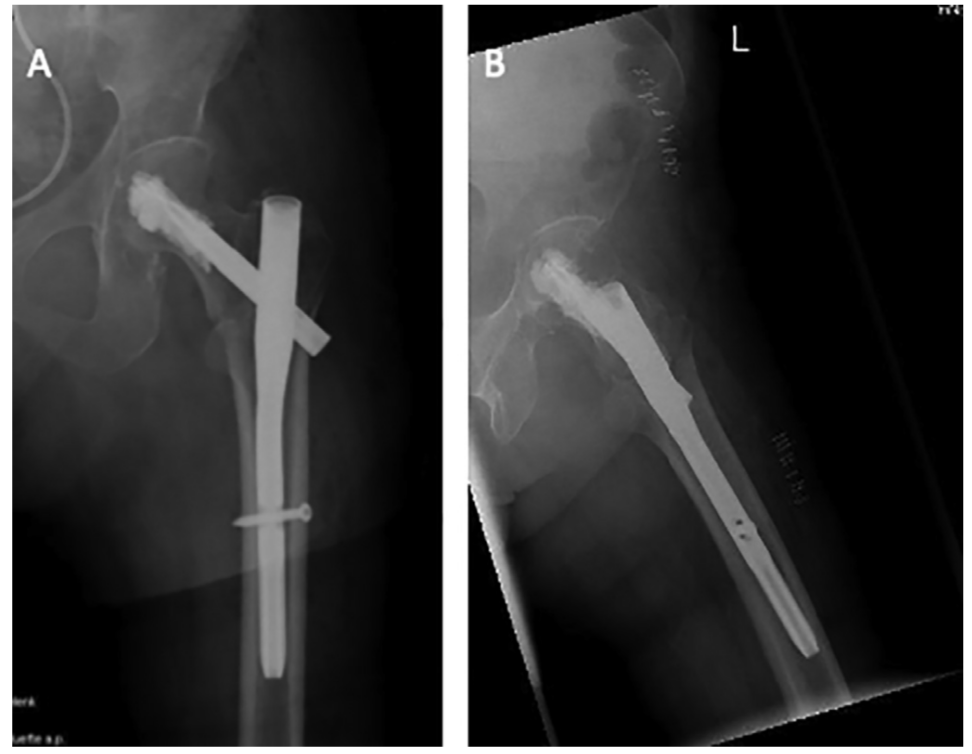

骨水泥加强的PFNA,能否增加老年患者早期负重能力?

股骨近端骨折是老龄患者最常见的骨折之一,其中50%累及转子周围区域。老龄患者骨质疏松,PFNA内固定术后早期功能锻炼可能导致螺钉切割、内固定失效等并发症,而早期功能锻炼对患者功能恢复至关重要。因此,有学者研究了骨水泥加强的PFNA,以评估能否增加老龄患者患肢早期的负重能力。